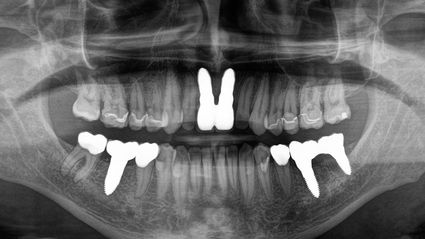

Mein erster Besuch war im Dezember 16. Ich ließ meine 4 Weisheitszähne reinigen, 3 weitere Kavitäten (von Zähnen, die im Sommer 16 in den USA gezogen worden waren) reinigen und Implantate einsetzen. Außerdem wurde eine Goldkrone und ein wenig Metall entfernt. Bei meinem letzten Besuch am 16. Juli haben wir verschiedene Zähne mit Kunststofffüllungen repariert und durch Keramikfüllungen und Kronen ersetzt. Vor allem aber zogen wir 2 Zähne, die tiefe Wurzelinfektionen aufwiesen, reinigten Karies und setzten 2 Implantate ein. Ich spürte fast sofort einen Seufzer der Erleichterung in meinem ganzen Körper. Dann ein Energieschub! Hier wird alles daran gesetzt, dass der Patient vor, während und nach dem Eingriff die besten Chancen auf Heilung und Genesung hat.